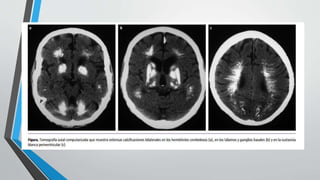

• La tomografía computarizada sin contraste, llega a ser el

método de diagnostico que nos ofrece mayor sensibilidad y

especificidad, nos demuestran las calcificaciones bilaterales y

simétricas de los talamos, sustancia blanca, ganglio basales y

cerebelo.